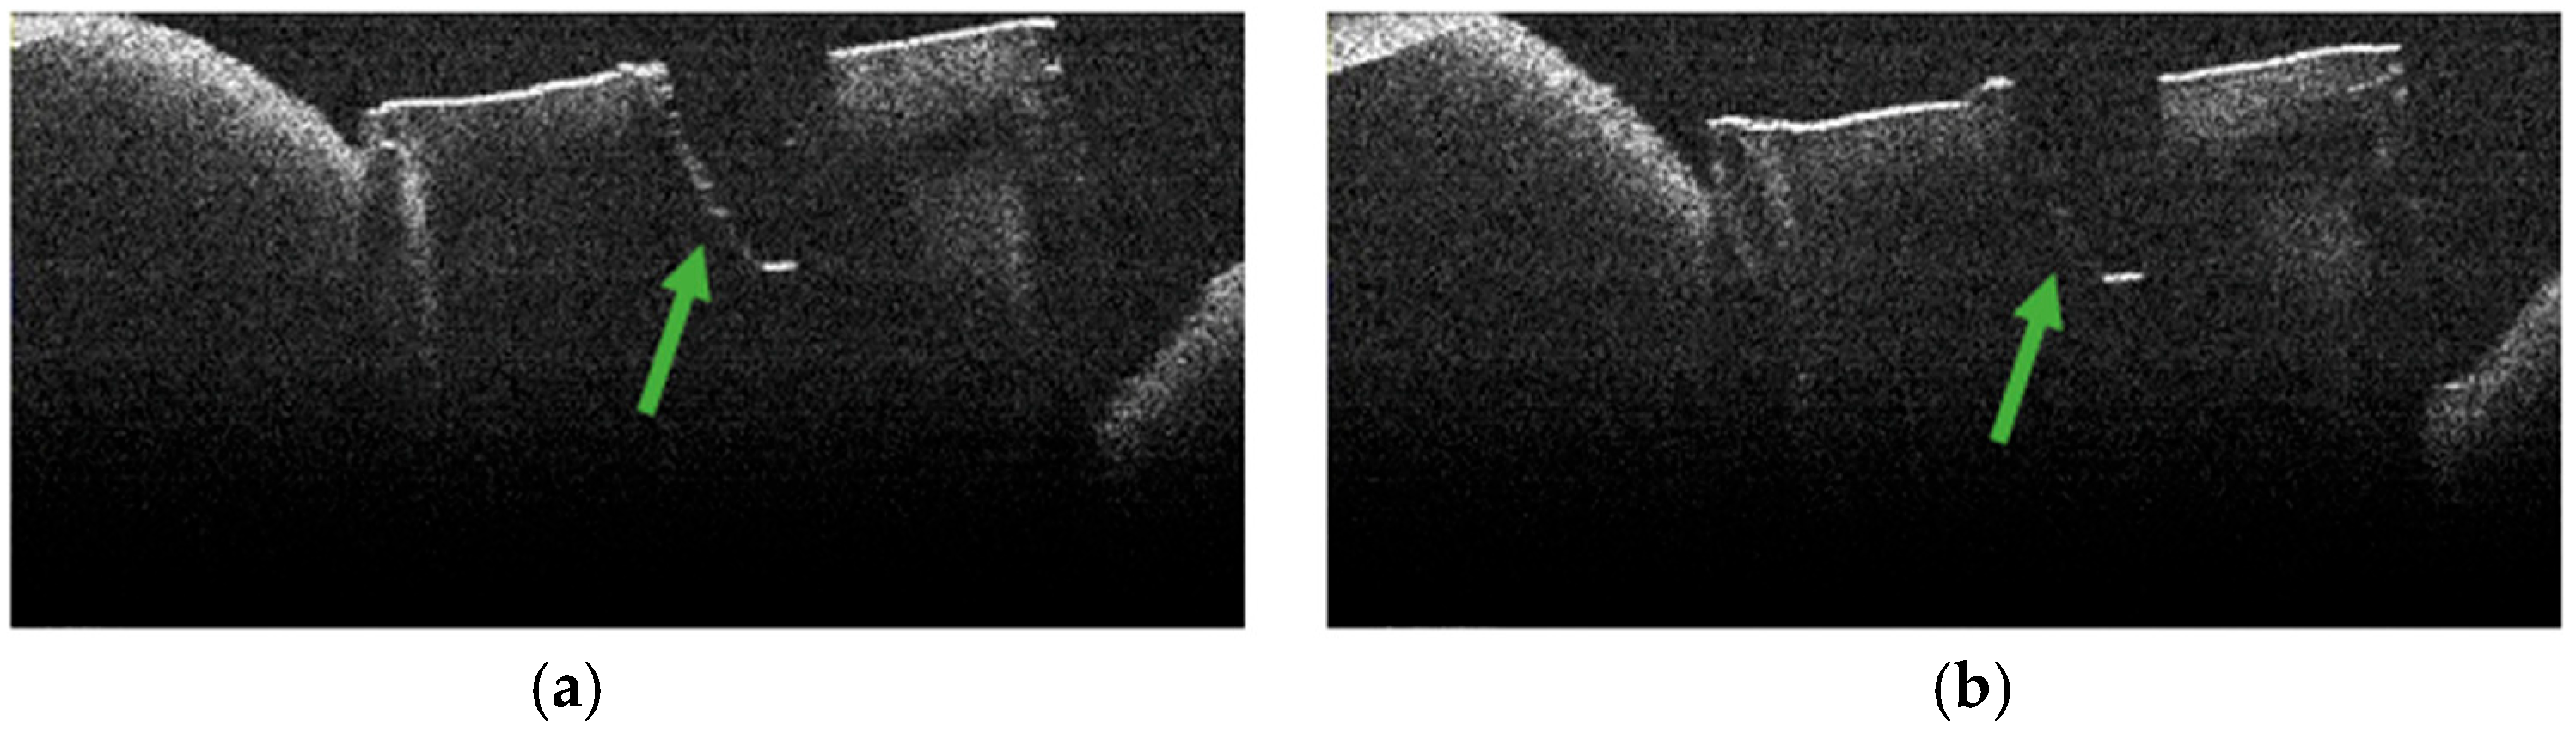

3.4. OCT Examination of Specimens from Group A

3.7. Frequency of TIMAs